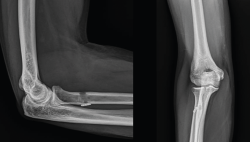

Las lesiones del tendón distal del bíceps varían desde la bursitis bicipitorradial hasta las roturas completas, pasando por las tendinosis y las lesiones parciales. Una buena historia clínica y una exploración física meticulosa aportan gran cantidad de información a la hora de orientar el diagnóstico, que se puede apoyar en la ecografía y la resonancia nuclear magnética para confirmar el diagnóstico y descartar otras entidades plausibles. En el caso de la bursitis bicipitorradial, la tendinosis y las lesiones parciales, el tratamiento inicial debe ser conservador salvo en casos concretos. Las roturas completas agudas deben tratarse de forma quirúrgica excepto en pacientes con baja demanda física o no aptos para tratamiento quirúrgico, sin sobrepasar las 4 semanas de evolución. En caso de diagnóstico tardío y roturas crónicas, las alternativas son la reparación primaria o la reconstrucción con autoinjerto o aloinjerto. Tras la cirugía, es imprescindible seguir un protocolo de rehabilitación que progrese en la ganancia del balance articular y la fuerza sin alterar el proceso de cicatrización. El objetivo de este artículo es presentar las distintas lesiones del bíceps distal, los métodos diagnósticos más adecuados y las alternativas terapéuticas para cada una de las entidades patológicas, para lo que se ha llevado a cabo una revisión bibliográfica a través del motor de búsqueda PubMed de artículos en inglés con referencia al tema seleccionado.

Distal biceps tendon injuries vary from bicipitoradial bursitis to complete rupture, including tendinosis and partial rupture. A good patient history and physical examination provide a great amount of information when trying to establish diagnosis helped by ultrasound and MRI to confirm our suspicion and make a differential diagnosis. Initial treatment for bicipitoradial bursitis, tendinosis and partial rupture should be conservative except in some concrete patients. Complete acute ruptures should be managed by surgical treatment except in low demand patients or patients with concerns regarding anesthesia or surgery. This surgery should be performed before 4 weeks after initial trauma. In case of delayed diagnosis or chronic ruptures, the different alternatives are primary reparation or reconstruction with autograft or allograft. After surgery a rehabilitation program is essential to improve range of motion and strength without stressing the healing process. The main purpose of this manuscript is to present different distal biceps injuries, the most adequate ways to establish a diagnosis and treatment alternatives for every kind of lesion. That is why a revision has been performed through PubMed search engine regarding the selected issue.